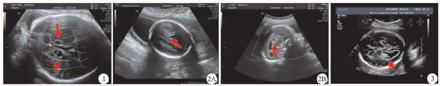

纳入研究的40例FICH胎儿中,胎儿超声检查提示FICH为33例,包括室管膜下稍强回声(3例)、无回声(1例);脑室内稍强回声(10例)、不均匀回声(2例);脉络丛稍强回声(2例)、无回声(2例)、弱回声(1例)、不均匀回声(3例);脑实质稍强回声(3例)、无回声(2例)、弱回声(2例)、不均匀回声(2例)。胎儿超声对FICH内部及周边均未探及血流信号。其余7例胎儿超声检查结果均提示颅内结构异常。33例FICH胎儿的超声检查头颅声像特征,见表1及图1,图2,图3,图4。

本研究纳入40例FICH中,FICH发生部位、回声,主要与颅内出血量及出血发生时胎龄有关[14]。FICH的典型头颅超声声像图特征为边界清楚的强回声,但是可随着颅内出血量与出血时间变化而变化,具体如下:①在颅内出血发生的1周内,出血灶表现为强回声,回声均匀;②出血1~2周后,出血灶可表现为部分液化吸收而呈不均匀的混合回声,内部可呈无回声;③出血1~3个月后,出血灶表现为完全液化而呈无回声区,内部可见絮状或条索样强回声,此为液化吸收后形成的纤维组织;④出血超过3个月,出血少的血块可机化或消失,脑组织可逐渐恢复正常[15]。FICH可发生在室管膜下、脑室、脉络丛及脑实质内,根据出血进展,胎儿头颅超声声像图特征可表现为稍强回声、无回声、弱回声及不均匀回声[16]。

由于FICH时期不同,胎儿超声声像图存在差异。中、晚孕期胎儿超声诊断不同分期FICH的标准具体如下:①FICH初期,血块呈强回声;②FICH液化期,回声减低,呈低回声或混合回声;③FICH完全液化期,血块被吸收呈低回声或无回声,显示血块内部及周边,均未探及血流信号[6]。